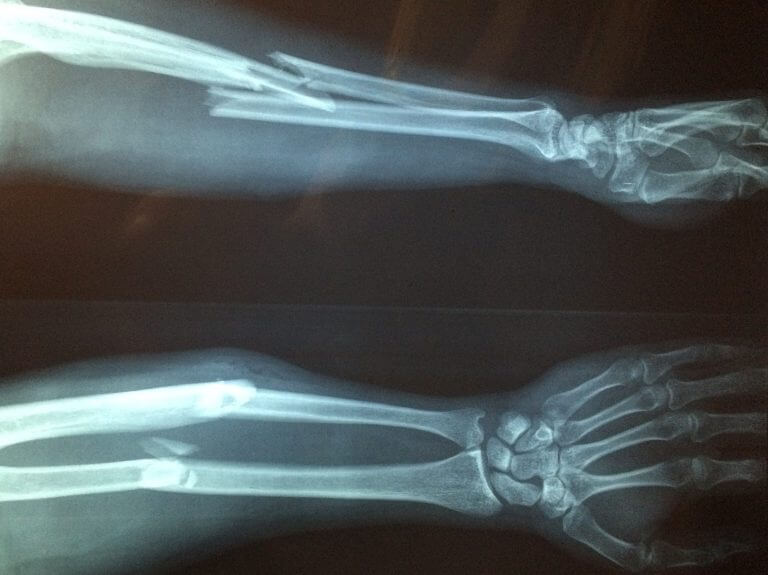

אוסטאופורוזיס הוא הגורם הנפוץ ביותר לעצמות שבורות אצל קשישים משני המינים. אילוסטרציה: pixabay.

זיהום חודר עצמות

עצמות ניאנדרטל שחי לפני 120 אלף שנה באיזור שהיום הוא קרואטיה, ועליהן גידול סרטני. צילום: Janet Monge et al

נמצא גידול סרטני בן 120 אלף שנה בעצמות ניאנדרטל